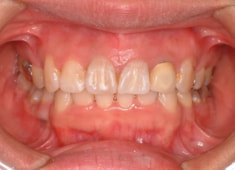

治療前